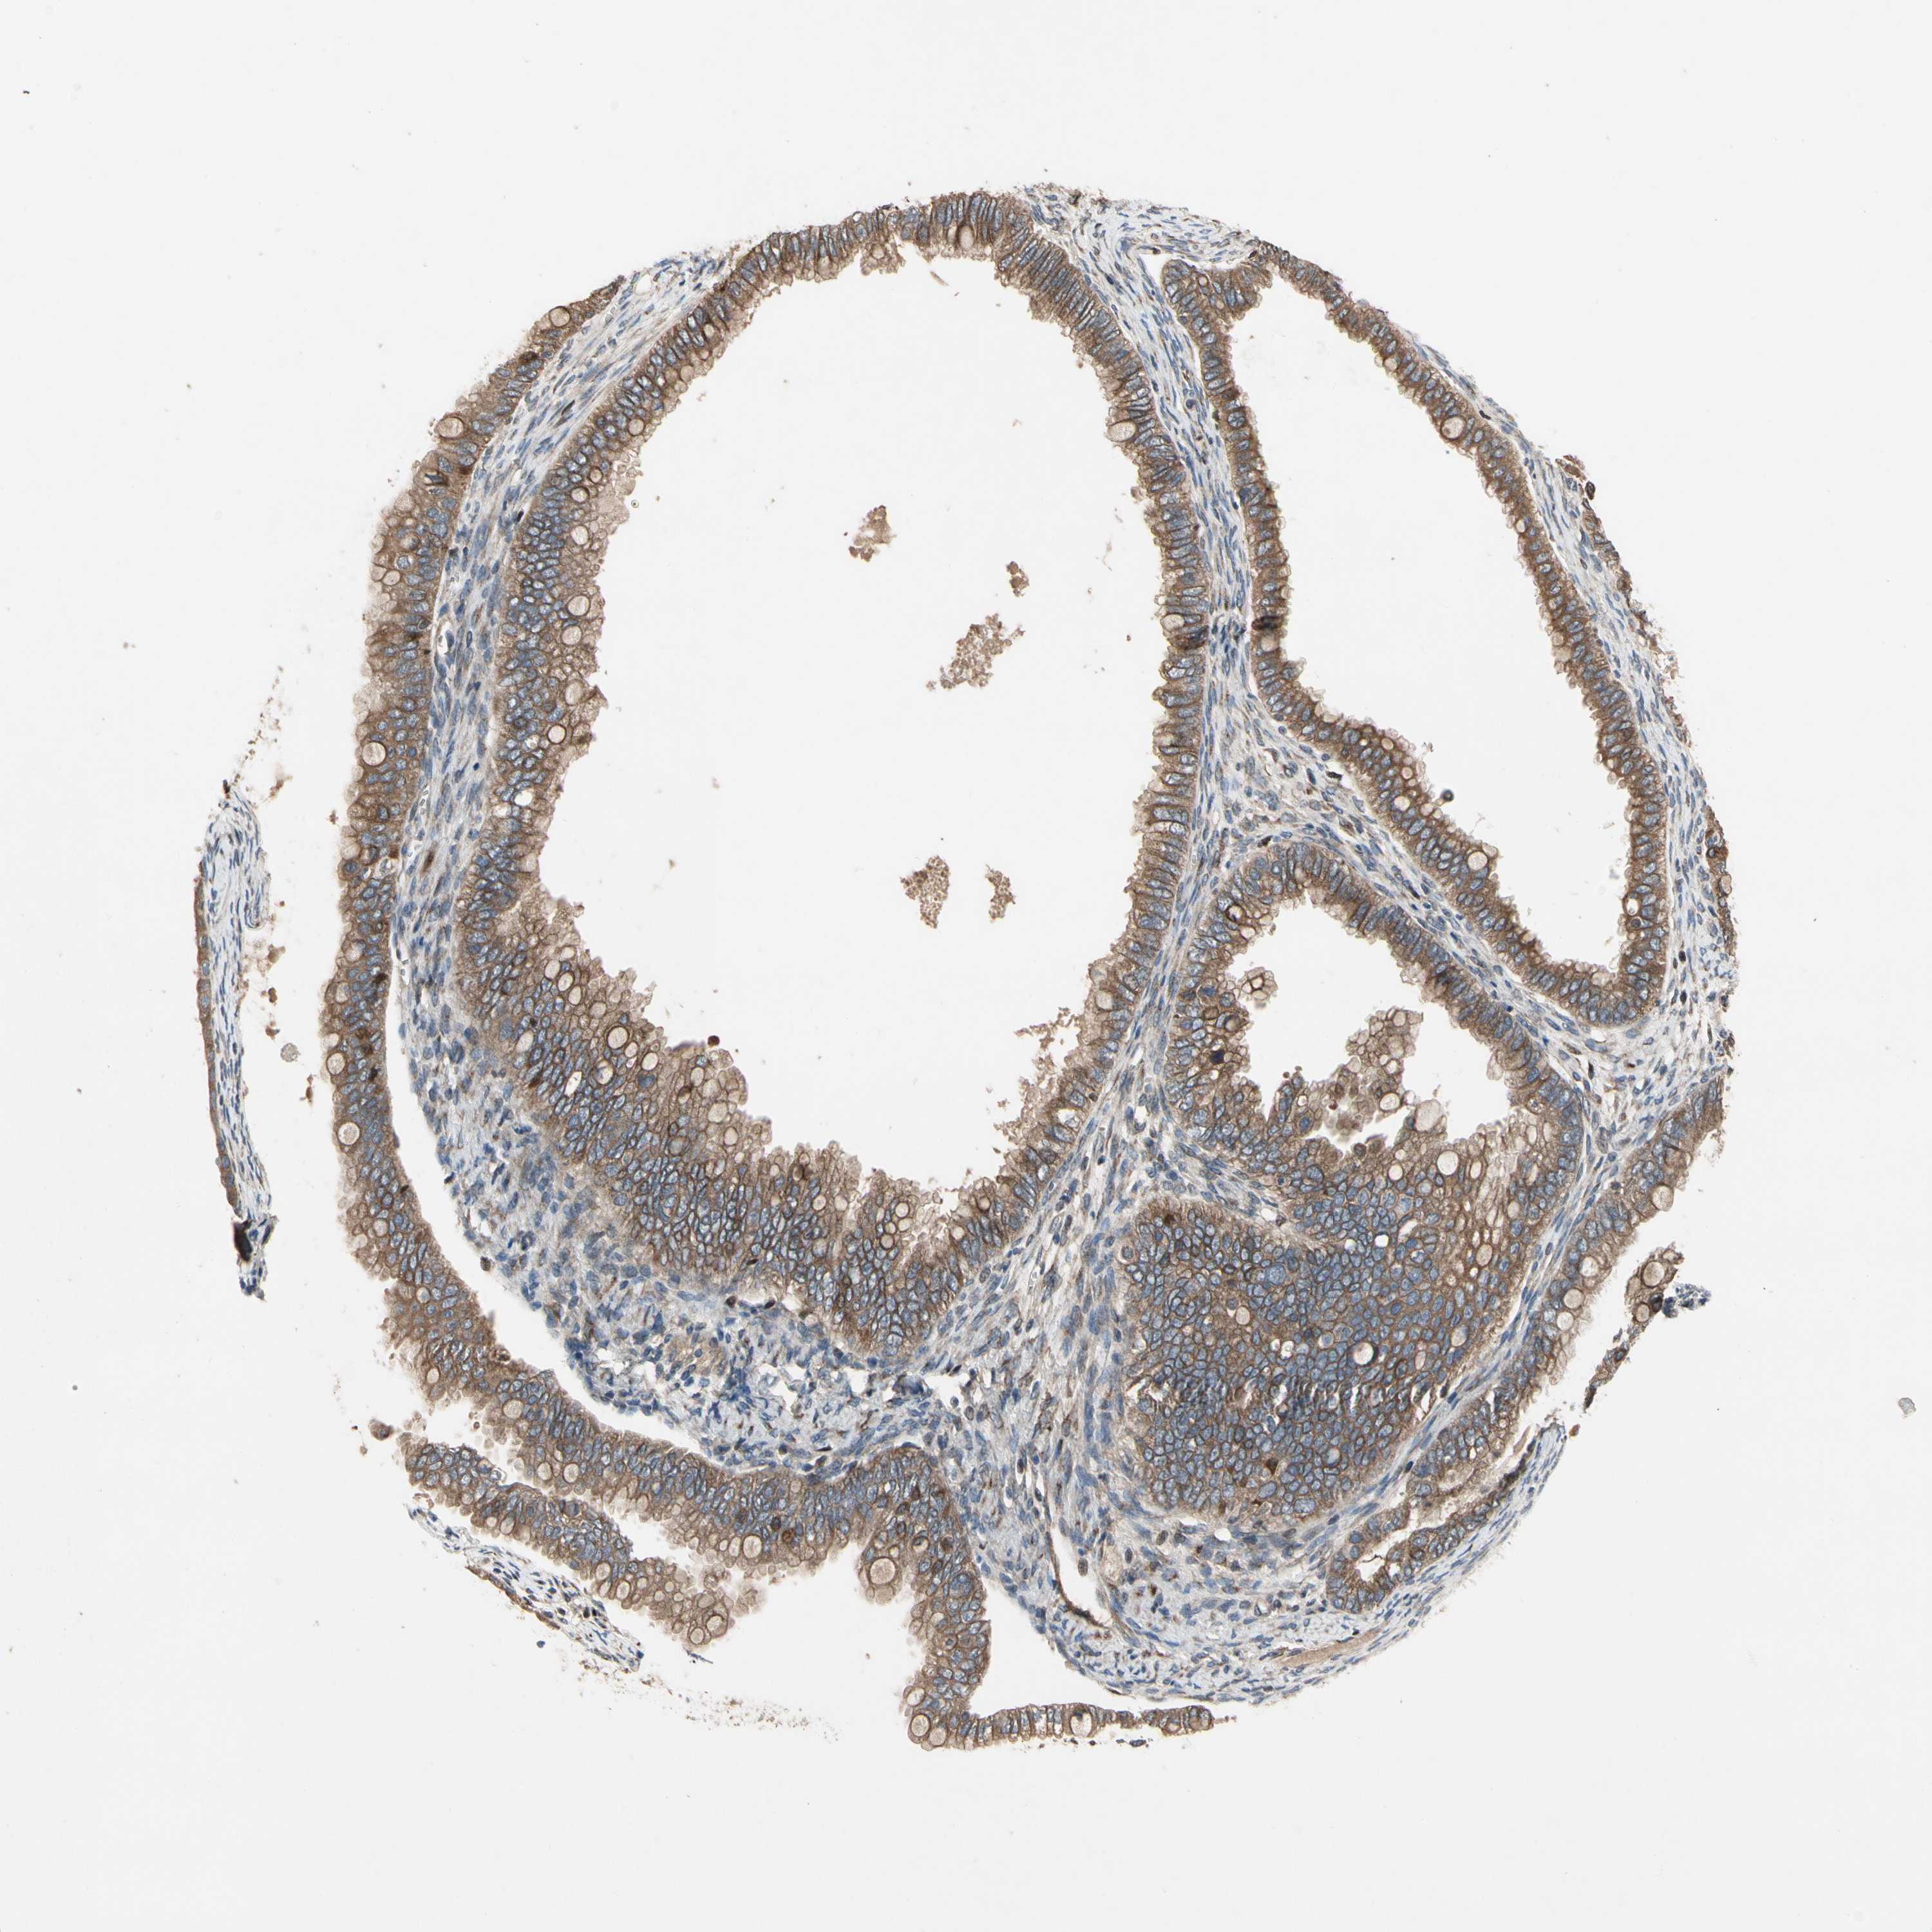

OVARIAN CANCER - Protein expressioni

A mouse-over function shows sample information and annotation data. Click on an image to view it in a full screen mode. Samples can be filtered based on level of antibody staining by selecting one or several of the following categories: high, medium, low and not detected. The assay and annotation is described here.

Note that samples used for immunohistochemistry by the Human Protein Atlas do not correspond to samples in the TCGA dataset.

Antibody stainingi

Antibody staining in the annotated cell types in the current human tissue is reported as not detected, low, medium, or high, based on conventional immunohistochemistry profiling in selected tissues. This score is based on the combination of the staining intensity and fraction of stained cells.

Each image is clickable and will lead to virtual microscopy that enables deeper exploration of all samples and also displays staining intensity scores, fraction scores and subcellular localization as well as patient and tissue information for each sample.

Antibody HPA008241

Staining

High

Medium

Low

Not detected

Intensity

Strong

Moderate

Weak

Negative

Quantity

>75%

75%-25%

<25%

None

Location

Nuclear

Cytoplasmic/membranous

Cytoplasmic/membranous,nuclear

Cystadenocarcinoma, serous, NOS

Carcinoma, endometroid

Cystadenocarcinoma, mucinous, NOS

Carcinoma, NOS